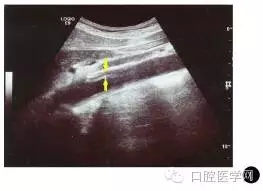

血常規(guī)檢查:CRP45.49mg/L,ESR45mm/h,均異常增高。動(dòng)脈超聲檢查示升主動(dòng)脈、頭臂干、腹主動(dòng)脈中段(圖1)及左側(cè)腎動(dòng)脈等大動(dòng)脈的血管壁明顯增厚。

圖1患者腹主動(dòng)脈的血管超聲圖(箭頭示增厚的血管壁)